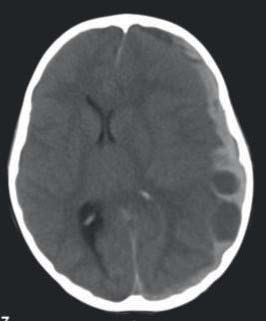

Na TC-CE, realizada duas horas após admissão na UCIP, apresentava hematoma subdural agudo à esquerda com desvio da linha média e sinais de encravamento do uncus (Figura 1).

FIGURA 1 - Hematoma subdural agudo, hemisfério esquerdo, com desvio da linha médica, em TC-CE, corte axial